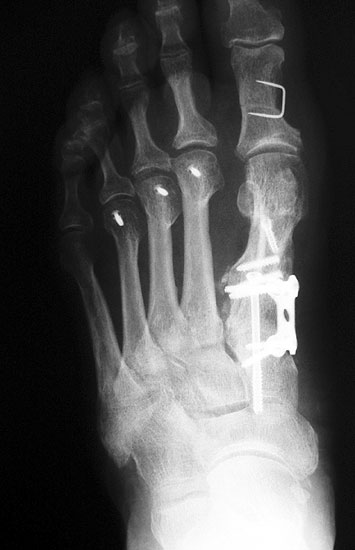

Die Röntgenaufnahmen (Abbildung 1) zeigen den Fuß einer 34 jährigen Patientin nach Exostosenabtragung. Der erhöhte intermetatarsale Winkel wurde durch eine alleinige Abtragung der Exostose nicht reduziert. Als weiterer Risikofaktor für ein Rezidiv liegt ein pathologischer Gelenkwinkel vor. Der intermetatarsale Winkel von 18 Grad kann durch eine basisnahe Osteotomie gut korrigiert werden. Da durch die gleichzeitige distale Korrektur des Gelenkflächenwinkels mithilfe einer Reverden-Green Osteotomie ein Längenverlust von ca. 2-4 mm einhergeht, bot sich als proximales Korrekturverfahren die basisnahe Open-wedge Osteotomie an, um bezüglich der Länge des Metatarsale I neutral zu bleiben (Abbildung 2). Die Kombination zweier verkürzender Verfahren (z.B. Lapidus und Reverden-Green) würden zu einem sehr kurzen ersten Strahl führen, mit dem Risiko einer Transfermetatarsalgie. Übersteigt die Verkürzung des Metatarsale I 2 mm, steigt das Risiko für die Entwicklung einer Transfermetatarsalgie deutlich an 8. Die durchgeführte Revision zeigt eine gute Stellung des 1. Strahls bei zentriert stehendem Gelenk.